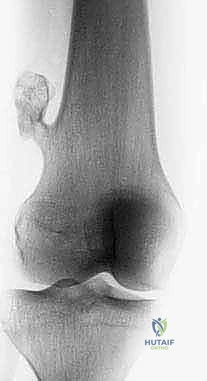

الحالة الأولى: إنقاذ ركبة رياضي شاب

شاب يبلغ من العمر 19 عاماً عانى من ألم مستمر في الركبة وتورم لم يستجب للمسكنات. بعد الفحص السريري الدقيق وإجراء الرنين المغناطيسي، اشتبه الأستاذ الدكتور محمد هطيف بوجود ورم. تم إجراء خزعة إبرة أساسية دقيقة جداً. أظهرت النتائج وجود "ساركوما عظمية" في مراحلها الأولى. بفضل الخزعة الدقيقة التي لم تلوث الأنسجة المحيطة، تمكن الدكتور هطيف لاحقاً من استئصال الورم بالكامل وتركيب مفصل صناعي خاص بالأورام، مما أنقذ ساق الشاب من البتر ومكنه من العودة للمشي بشكل طبيعي.